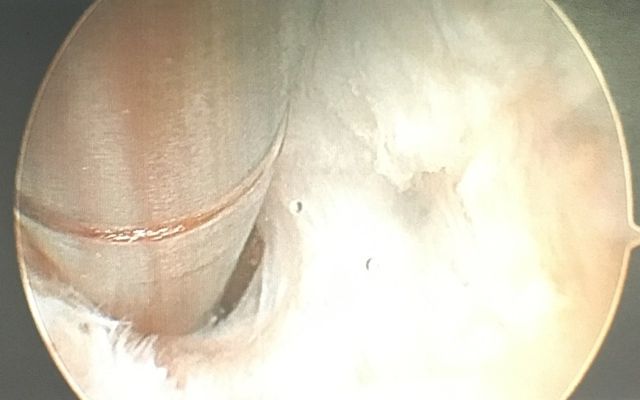

Kann konservativ keine Verbesserung erreicht werden, stellt die Sehnenkerbung der Plantaraponeurose, am besten unter arthroskopischer Kontrolle, eine effektive Therapievariante dar.

Diese wird normalerweise kombiniert mit einer arthroskopisch kontrollierten Knochenspornabtragung am Fersenbein, um eine neuerliche Druckproblematik verhindern zu können.